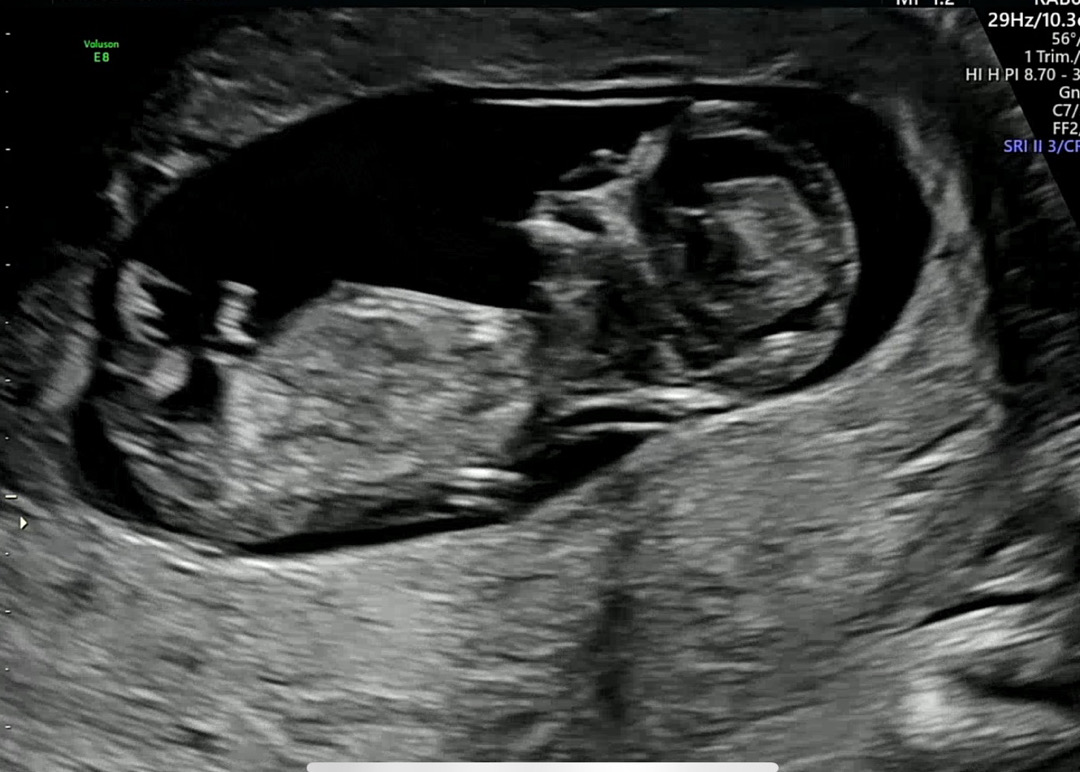

(12주1일) 아들 딸 너무 궁금하네요 ㅎㅎㅎ🫶☺️

딸 아들 상관은 없는뎅 궁금해요 신랑은 아들같다는데 이말듣규 서운한거보니 딸이면 좋겟다 싶기도하네요